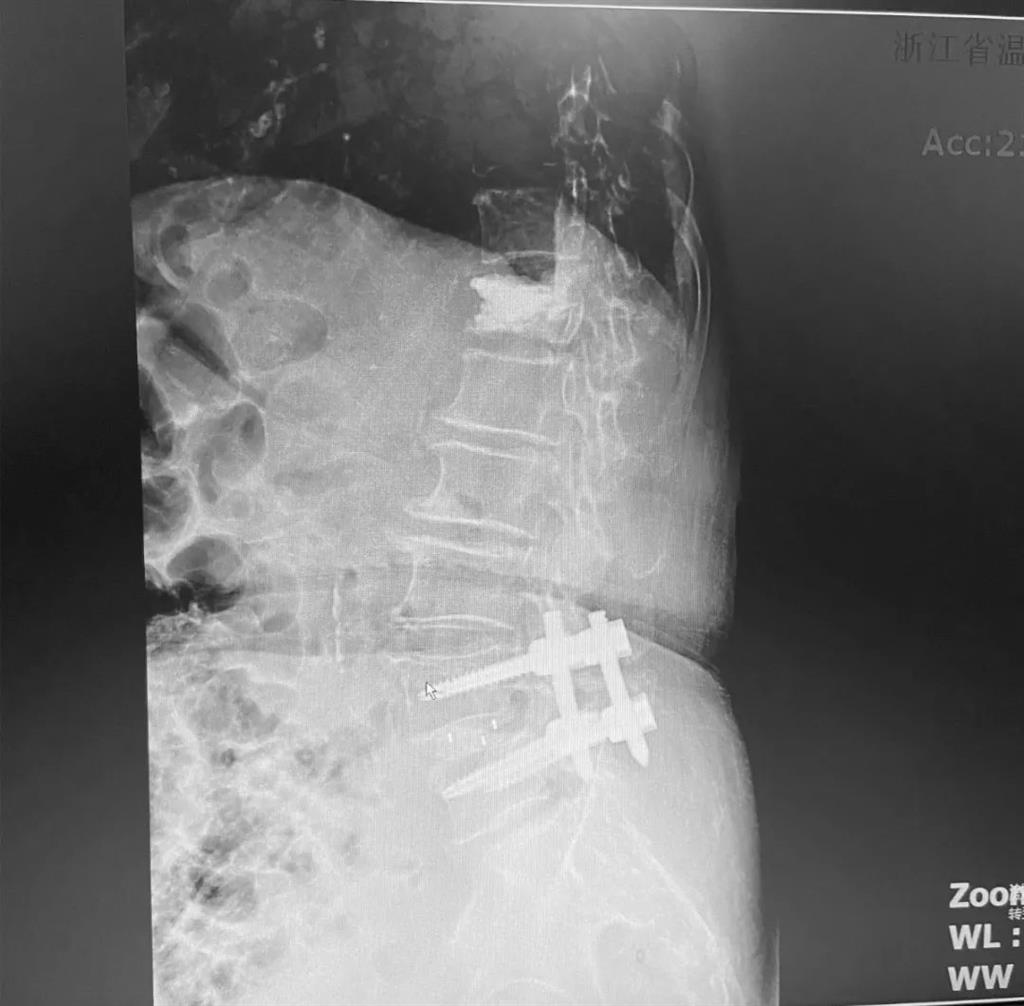

據(jù)了解,脊柱內(nèi)鏡下腰椎融合術(shù)只需要打幾個(gè)“鑰匙孔”即可完成。聽(tīng)起來(lái)是不是很簡(jiǎn)單?在脊柱內(nèi)鏡下,劉丹主任先后為患者進(jìn)行了椎管減壓、椎間盤摘除,再實(shí)施椎弓根螺釘放置、椎體植骨融合內(nèi)固定,一系列步驟有條不紊。

看似簡(jiǎn)單的幾個(gè)步驟,但實(shí)際上很復(fù)雜,需要主刀醫(yī)生有豐富的手術(shù)經(jīng)驗(yàn)和細(xì)致耐心的操作。

而脊柱內(nèi)鏡下腰椎融合術(shù),作為目前國(guó)內(nèi)脊柱微創(chuàng)領(lǐng)域大力發(fā)展的新技術(shù),徹底改變了傳統(tǒng)開(kāi)刀椎板切除椎間植骨融合內(nèi)固定的大創(chuàng)傷現(xiàn)狀,可以在較大程度上減少對(duì)脊柱后方穩(wěn)定結(jié)構(gòu)的破壞,創(chuàng)傷小,出血少,術(shù)后恢復(fù)快。

術(shù)中只需切開(kāi)4個(gè)如“鑰匙孔”般大小的孔道